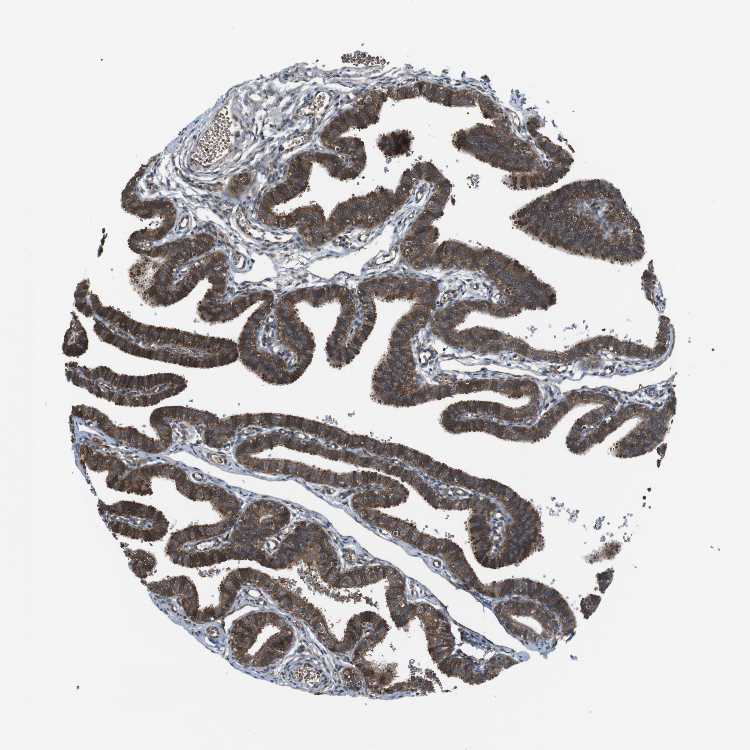

FALLOPIAN TUBE - Antibody stainingi

Antibody staining in the annotated cell types in the current human tissue is reported as not detected, low, medium, or high, based on conventional immunohistochemistry profiling in selected tissues. This score is based on the combination of the staining intensity and fraction of stained cells.

Each image is clickable and will lead to virtual microscopy that enables deeper exploration of all samples and also displays staining intensity scores, fraction scores and subcellular localization as well as patient and tissue information for each sample.

Antibody HPA014906

Glandular cells High